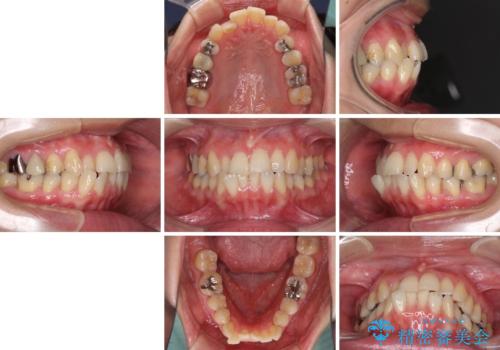

- 前歯のデコボコを気にして来院された患者様です。

上下前歯の先端同士が接触する切端咬合であったため、上顎は歯列を拡大し、下顎はIPR(歯と歯の間を削る)により叢生を解消しながら歯列を小さくすることとしました。

矯正装置にはインビザラインを用いることとしました。

治療途中に前歯に歯髄充血を思わせる痛みが認められたため、無理のない歯の移動と頻繁な経過観察を行いました。

切端咬合はスムーズに解消され、前歯の負担を軽減させることができました。